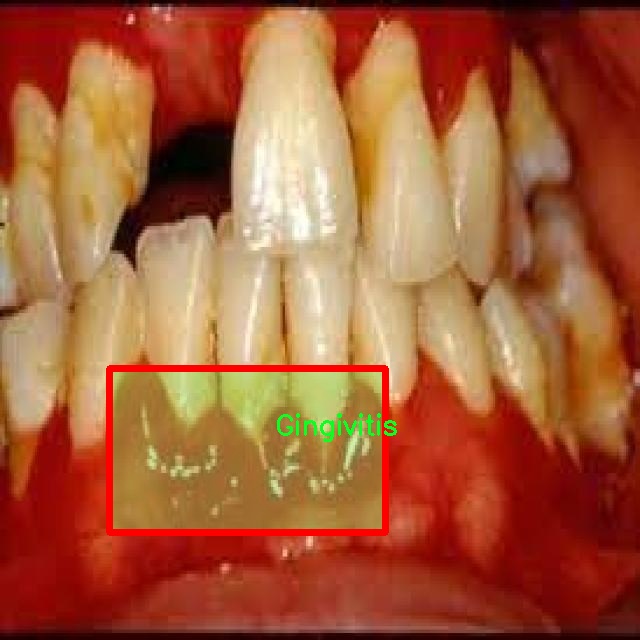

图片效果

在这里插入图片描述

在本研究中,我们使用了名为“unbeknownst to man”的数据集,旨在改进YOLOv8-seg的口腔疾病图像分割系统。该数据集专注于口腔健康领域,涵盖了四种主要的口腔疾病类别,分别是龋齿(Caries)、牙龈炎(Gingivitis)、牙齿变色(Tooth Discoloration)和溃疡(Ulcer)。这些类别的选择不仅反映了口腔疾病的多样性,也为我们提供了一个全面的视角,以便更好地理解和分析这些疾病的表现形式及其在图像中的特征。

数据集中的每个类别都包含大量高质量的图像,这些图像经过精心标注,确保了每个样本的准确性和一致性。龋齿作为最常见的口腔疾病之一,其图像展示了不同阶段的龋齿发展,从初期的微小白斑到严重的牙体损坏,图像中清晰的细节为模型训练提供了丰富的信息。牙龈炎则通过展示红肿、出血等症状,帮助模型学习如何识别和分割出受影响的牙龈区域。牙齿变色的图像则展示了因多种因素导致的牙齿色泽变化,这些变化可能是由于饮食、生活习惯或口腔卫生不良等原因引起的。最后,溃疡的图像则提供了对口腔内病变的直观表现,通常伴随着疼痛和不适,这类图像的标注对于识别和分割至关重要。